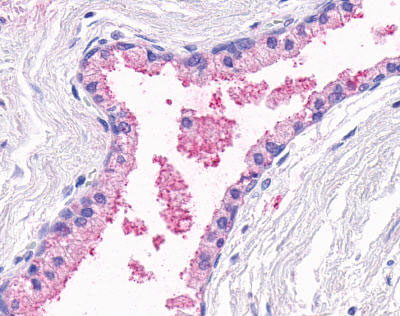

Anti-OR51E1 antibody APR12581G IHC of human prostate, glands. |